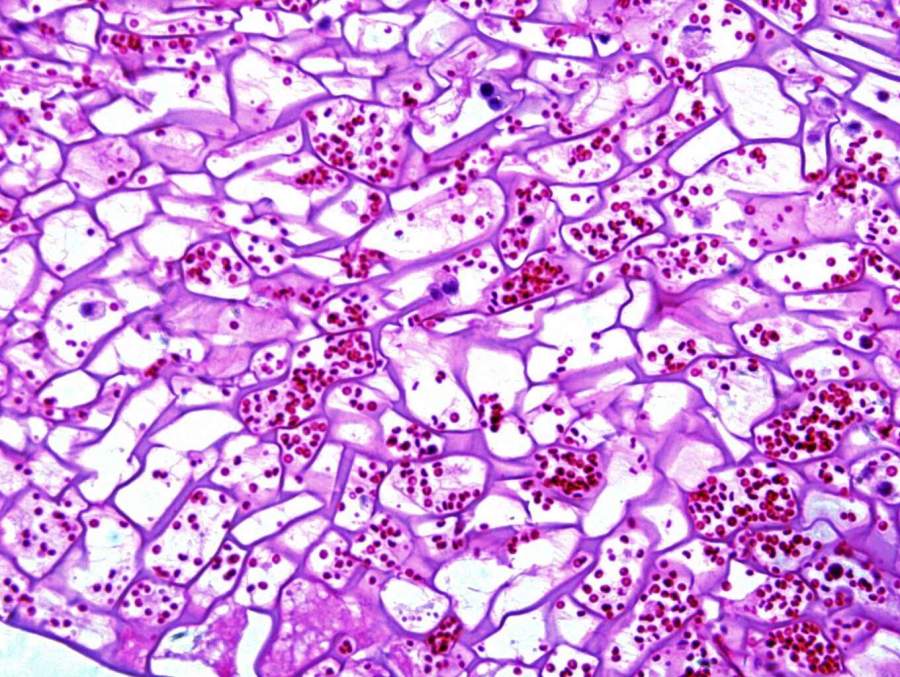

各大神,求分析图片中是不是炎症细胞?! 发自小木虫Android客户端 |